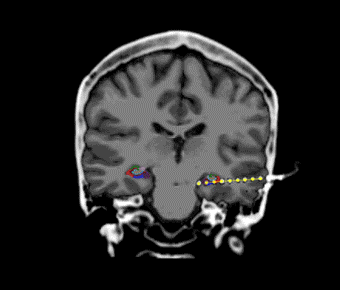

We study how our perception and spontaneous behavior are reflected in neuronal activity. Our overall aim is to understand how visual images and free behaviors emerge from such patterns of activity.